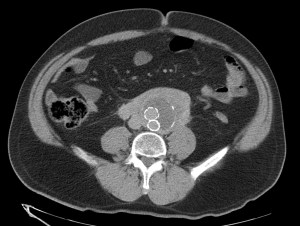

SIGNO DE LA AORTA FLOTANTE (Floating aorta sign):

Representa el crecimiento y coalescencia de conglomerados adenopáticos que desplazan la aorta lumbar hacia adelante, despegándola de la columna. Este signo lo producen algunos tumores, en especial el Linfoma. Así, da la impresión de que la aorta está «flotando» inmersa en una masa de partes blandas retroperitoneal que se ha formado por el crecimiento de las adenopatías de las cadenas periaórticas, pericavas e interaortocavas, las cuales finalmente se han unido. Otro signo muy útil es el signo del Sandwich, donde se observa, en un TC con contraste, como la masa envuelve los vasos y la grasa del mesenterio.

Aparte del linfoma, en las otras etiologías, puede no existir el desplazamiento de la aorta lumbar (algunas metástasis, fibrosis), puede haber menos coalescencia de los conglomerados adenopáticos (TBC, micobacaterias atípicas), puede observarse áreas hipoatenuadas en su interior de necrosis (leiomiosarcoma) o con densidad grasa (liposarcoma) o las adenopatías pueden tener un realce ávido de contraste (E. de Castleman). En la fibrosis retroperitoneal la atenuación con contraste es más uniforme, la localización suele ser infrarrenal, sin desplazamiento anterior de aorta y con afectación de uréteres. Las posibilidades son numerosas y cada una tiene sus características.